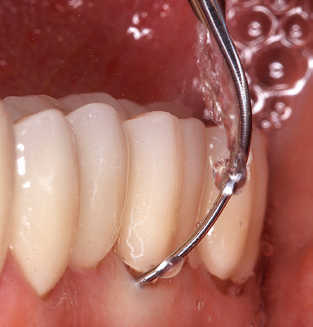

The current working concept for SPT

Updating the patient’s medical history is an important aspect of SPT and should occur at least once per year. It helps the dental team to identify and document any new risk factors. Especially when a patient is treated over many years, it is important to establish whether patient-specific and general health risk factors have changed. This primarily concerns a heightened risk as a result of diabetes, but other general conditions (cardiovascular disease and neoplasia) can also produce a modified risk profile as a result of the treatment performed and medication administered. Accordingly, updating the medical history as part of SPT is very important, as a modified risk profile may trigger the need to adapt the treatment interval. In the next step, it is important to afford the diagnostics due attention. Whilst instruments are a central aspect of SPT, findings and their documentation must never be neglected. The periodontological findings are essential for a good diagnosis; increases in the pocket depths and the BOP index are clear indicators of advancing periodontal and peri-implant disease. As such, the team should not shy away from probing implants too, with the aim of gathering the requisite data. At the same time, it is important to use periodontal probes with millimetre markings. Metallic probes have already been used for determining pocket depths around natural teeth for decades. In the case of implants, the challenge of recording correct and reproducible pockets depths is even greater. As the discrepancy between the implant diameter and the contour of the superstructure regularly results in overcontouring of the superstructure, flexible probes which still feature millimetre markings are a sensible solution for measuring pocket depths around implants (e.g., Colorvue Kit PCV11KIT6, Hu­Friedy; Fig. 4).

Fig. 4: Flexible probes with millimetre markings are recommended for the probing of dental implants (e.g. Colorvue Kit PCV11KIT6, Hu­Friedy). – Fig. 5a and b: A straight working tip (1P, W&H Dentalwerk Bürmoos GmbH) is a suitable instrument for use on all natural teeth. – Fig. 6: Curved working tips (3Pr/3Pl, W&H Dentalwerk Bürmoos GmbH) lend themselves to the processing of difficult-to-reach areas of the tooth and root surfaces (e.g. furcations). – Fig. 7: The tapered, hexagonal implant cleaning tip (1I, W&H Dentalwerk Bürmoos GmbH) permits atraumatic and efficient cleaning of the crown and abutment surfaces. – Fig. 8: Titanium and carbon curettes are suitable instruments for the manual cleaning of the implant surfaces.